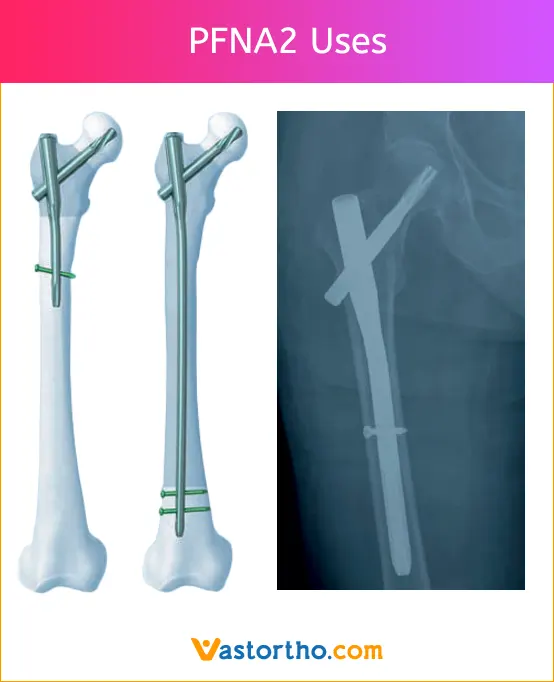

PFNA2 (Proximal femoral nail antirotation for Asia) has been developed especially for Asian patients.

The treatment of proximal femoral fractures in geriatric osteoporotic patients continues to be a challenge in orthopedic trauma. Various kinds of cephalomedullary nails, such as gamma nail, InterTan and PFNA were used clinically. The latest generation PFNA2, specially designed for Asian population, is commonly used for geriatric per-/intertrochanteric fractures. Some clinical studies have previously reported that the short-term clinical outcomes of PFNA2 are satisfactory in most patients, and it provides an anatomy matched with the narrower and shorter femurs of Asians and contributes to decreased complications.

PFNA2 Nail Uses

PFNA2 short (Length 170 mm – 240 mm)

Indications

1. Pertrochanteric fractures

2. Intertrochanteric fractures

3. High subtrochanteric fractures

Contraindications

1. Low subtrochanteric fractures

2. Femoral shaft fractures

3. Isolated or combined medial femoral neck fractures

PFNA2 long (Length 260 mm – 420 mm)

1. Low and extended subtrochanteric fractures

2. Ipsilateral trochanteric fractures

3. Combination fractures (in the proximal femur)

4. Pathological fractures

1. Isolated or combined medial femoral neck fractures